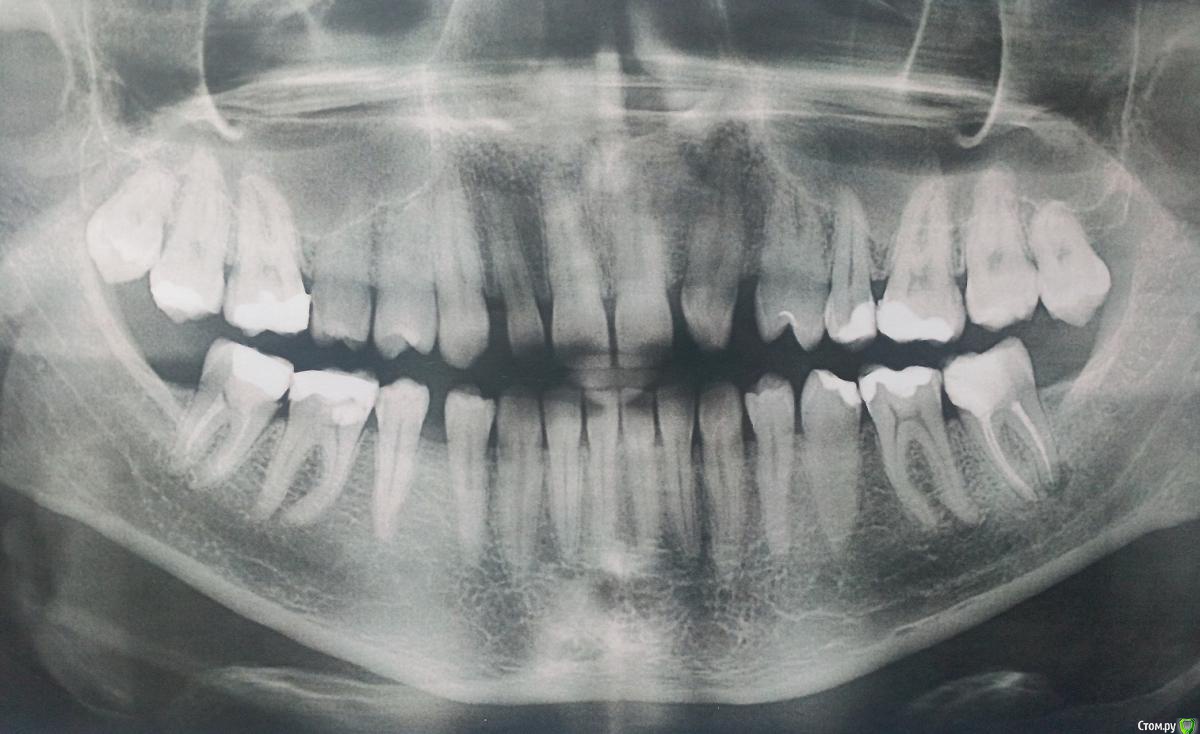

sergemiko Опубликовано 20 февраля, 2018 Поделиться Опубликовано 20 февраля, 2018 (изменено) Добрый день. Планирую ставить брекеты (на 2 года, самому 27 лет, муж.), но для полной красоты не хватает 12 зуба. Врач предложил сместить брекетами зубы друг к другу, либо, наоборот, раздвинуть для импланта на место отсутствующего 22 и коронки под 12 зуб. Вот, хочу посоветоваться, как лучше поступить.18 и 28 зубы уже удалены, собственно, я думаю, именно они, прорезываясь, сместили зубы в кривизну, но брекеты я решил ставить ещё до этого.37 зуб сделал доп.снимок, который показал, что воспаление не ярко выражено как на панорамном снимке, решили его не трогать.PS: немного смущают дёсна, кажется что оголились или это норма? Изменено 20 февраля, 2018 пользователем sergemiko Ссылка на комментарий

Дмитрий Л. Опубликовано 20 февраля, 2018 Поделиться Опубликовано 20 февраля, 2018 Вы наверное запутались с номерами зубов.Имплант лучше ставить подальше. Если есть возможность сместить ваш левый клык вперёд и запротезировать его под резец, а на место сдвинутого клыка поставить имплантат, то лучше делать так. В идеале фронт под виниры. По фото судить трудно, вашем врачу виднее ситуация. Ссылка на комментарий

sergemiko Опубликовано 20 февраля, 2018 Автор Поделиться Опубликовано 20 февраля, 2018 Вы наверное запутались с номерами зубов.Имплант лучше ставить подальше. Если есть возможность сместить ваш левый клык вперёд и запротезировать его под резец, а на место сдвинутого клыка поставить имплантат, то лучше делать так. В идеале фронт под виниры. По фото судить трудно, вашем врачу виднее ситуация.Да, перепутал, не хватает 22 зуба, а не 12. А почему именно левый клык сместить вперёд и запротезировать его под резец, а на место сдвинутого клыка поставить имплантат, а не поставить резец-имплантат, сместив клык назад или не принципиально важно? Ведь с правой стороны резец есть. И, кстати, на правый резец ставится коронка или винир? Ссылка на комментарий

Дмитрий Л. Опубликовано 20 февраля, 2018 Поделиться Опубликовано 20 февраля, 2018 Да, перепутал, не хватает 22 зуба, а не 12. А почему именно левый клык сместить вперёд и запротезировать его под резец, а на место сдвинутого клыка поставить имплантат, а не поставить резец-имплантат, сместив клык назад или не принципиально важно? Ведь с правой стороны резец есть. И, кстати, на правый резец ставится коронка или винир?На родном зубе проще добиться эстетики. На правый резец скорее всего коронка, но это не важно, коронка и винир одинаково эстетичны и изготавливаются из одних и тех же материалов.И снова, вашему врачу виднее как лучше. Ссылка на комментарий

Bier Опубликовано 22 февраля, 2018 Поделиться Опубликовано 22 февраля, 2018 Я бы все же ставил клык на свое место и имплантировал резец. Условия хорошие, если нормально сделать, все получится. 1 Ссылка на комментарий